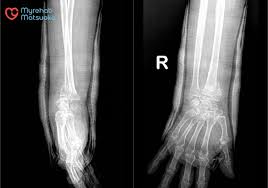

MYREHAB MATSUOKA phục hồi chức năng sau gãy xương TOÀN DIỆN theo tiêu chuẩn Nhật Bản

Dựa vào kết quả lượng giá và thăm khám ban đầu, bác sĩ sẽ chỉ định những bài tập và kỹ thuật vật lý trị liệu phù hợp với tình trạng sức khỏe của bệnh nhân sau gãy xương (cánh tay, đùi, mác,…). Thông qua kết quả trong từng buổi tập luyện tại MYREHAB MATSUOKA, bác sĩ sẽ điều chỉnh lộ trình và bài tập theo sự tăng tiến, khả năng hồi phục của bệnh nhân.

Phương pháp PHCN sau gãy xương tập trung vận động chủ động và vật lý trị liệu để tăng hiệu quả điều trị, hạn chế tác dụng phụ của thuốc và các biện pháp xâm lấn. Theo từng nhóm đối tượng mà bệnh nhân khi phục hồi chức năng sau gãy xương tại MYREHAB MATSUOKA sẽ được bác sĩ chỉ định các phương pháp trị liệu tương ứng sau: